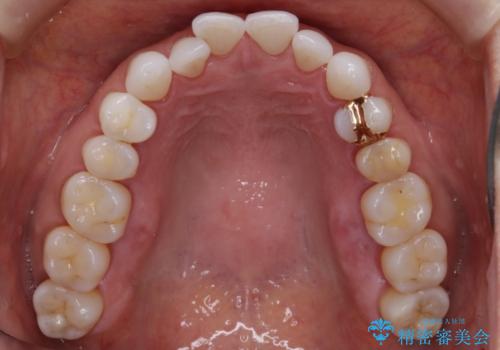

- 歯ぎしりや食いしばり、噛み合わせの治療とガタつきを治したいとのことでご来院されました。

検査の結果、前歯と臼歯の高さに差があり、前歯が全く当たらない状態になっているため歯ぎしりによって奥歯が削れてしまっているという状態でした。

マウスピースの矯正装置を用い、ガタつきを治しつつ奥歯を沈めていくことで噛み合わせ全体の改善を図りました。